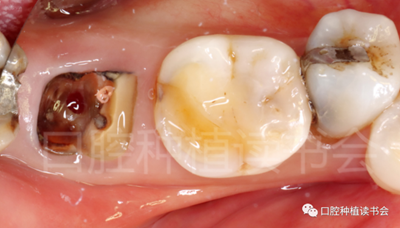

5.3.2 逐級預(yù)備種植窩洞后,側(cè)切鉆分根,微創(chuàng)拔除殘根,探查頰、舌側(cè)骨板完整,仔細(xì)搔刮拔牙窩,生理鹽水沖洗(圖15)。

圖15 微創(chuàng)拔牙后確認(rèn)種植窩洞位于牙槽間隔內(nèi)。

5.3.3 根據(jù)拔牙窩內(nèi)的牙槽間隔高度,植入康盛CANSUN柱形親水種植體(4.3*8mm),確保種植體肩臺與牙槽間隔平齊,種植體的所有表面均被自體骨包繞(圖16),植入扭矩為25N.cm。

圖16 盡量讓種植體表面被牙槽間隔的自體骨包繞。

5.3.4 旋入覆蓋螺絲,在種植體與四周骨壁的間隙內(nèi)植入 Bio-Oss Collagen,植骨材料用生理鹽水濕潤后,用15#刀片分割為小塊分別植入,并用充填器壓實(shí)(圖17)。

圖17 后牙即刻種植植骨推薦使用骨膠原材料,有利于軟組織愈合。

5.3.5 考慮到初始植入扭矩未達(dá)到30N.cm,采用外覆”倍菱“膠原蛋白+縫線固定的方式關(guān)閉創(chuàng)口的方案(圖18)。

圖18 創(chuàng)口使用”倍菱“膠原蛋白保護(hù),促進(jìn)愈合。